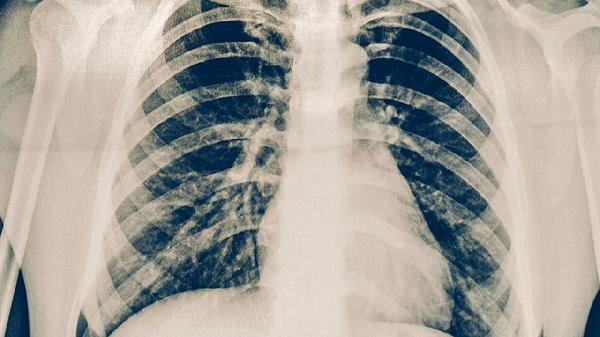

胸部CT通常可以查出肺癌,尤其是早期肺癌。胸部CT是篩查和診斷肺癌的重要手段之一,能夠發(fā)現(xiàn)肺部結(jié)節(jié)或腫塊,結(jié)合病理檢查可確診。

胸部CT通過(guò)高分辨率掃描能清晰顯示肺部結(jié)構(gòu),對(duì)直徑超過(guò)3毫米的結(jié)節(jié)檢出率較高。早期肺癌多表現(xiàn)為磨玻璃樣結(jié)節(jié)或?qū)嵭越Y(jié)節(jié),CT可評(píng)估其形態(tài)、邊緣及密度特征。對(duì)于中央型肺癌,CT能直接觀察到支氣管內(nèi)腫塊或管壁增厚,同時(shí)可判斷縱隔淋巴結(jié)轉(zhuǎn)移情況。增強(qiáng)CT還能通過(guò)血流動(dòng)力學(xué)變化鑒別良惡性病變。